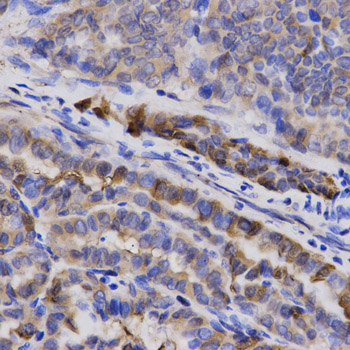

Immunohistochemistry - SNCG Polyclonal Antibody

Immunohistochemistry of paraffin-embedded human thyroid cancer using SNCG antibody at dilution of 1:200 (40x lens).